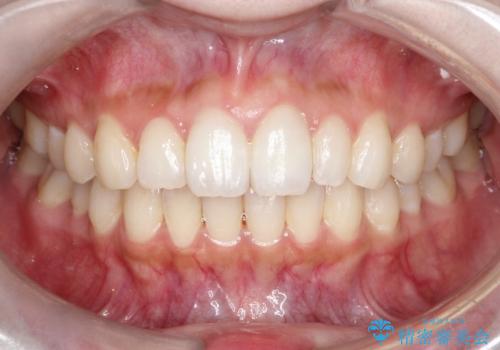

【インビザライン】矮小歯を有する方の治療②

- 前歯の凸凹を主訴に来院されました。

左上の前歯が元々小さいため、前歯の真ん中が揃わないことを伝えた上で矯正治療を開始しています。

スペースを作るために遠心移動ろIPRをおこなて治療を行いました。